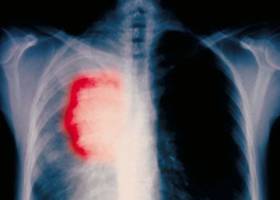

La principal causa del cáncer: el azar

Dos tercios de los cánceres no pueden prevenirse con el estilo de vida; la detección precoz es más esencial que nunca

Tradicionalmente se ha pensado que las mutaciones que causan el cáncer provienen de dos fuentes principales: la herencia y el ambiente (humo del tabaco, radiación ultravioleta de la luz solar y muchas otras). Un macroestudio coordinado por genetistas de la Johns Hopkins confirma ahora que no es así: dos tercios de las mutaciones cancerosas provienen de errores al azar en el proceso de replicación del ADN. Solo el tercio restante se debe a la herencia y al ambiente. Este hecho tiene importantes consecuencias para la prevención y tratamiento precoz de cada tipo de cáncer.

Una conclusión importante es que, pese a la importancia de las campañas para evitar el tabaco, el sol, las comidas grasas y demás, el foco se vuelve con más fuerza que nunca hacia la detección precoz. Porque, ni aun cuando esas campañas alcanzaran un éxito del 100%, lograrían evitar el 67% de los cánceres. Mal que les pese a los moralistas, la gran mayoría de los cánceres no son culpa de su víctima. Y solo detectarlos a tiempo podrá salvar a esos inocentes. Y de paso a los culpables que no logran vivir a la altura de las exigencias preventivas.